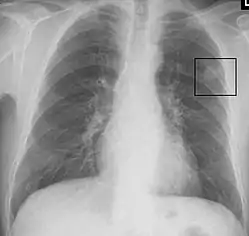

![]() الاشعة المقطعية الإكليلية مما يدل على ورم الظهارة المتوسطة الخبيثة

وسيلة الإيضاح: (الورم ★ الانصباب الجنبي المركزية)، 1 و3 الرئتين، 2 العمود الفقري، الأضلاع 4، 5 الشريان الأورطي، 6 الطحال، الكلى 7 و8 و9 الكبد. الاشعة المقطعية الإكليلية مما يدل على ورم الظهارة المتوسطة الخبيثة